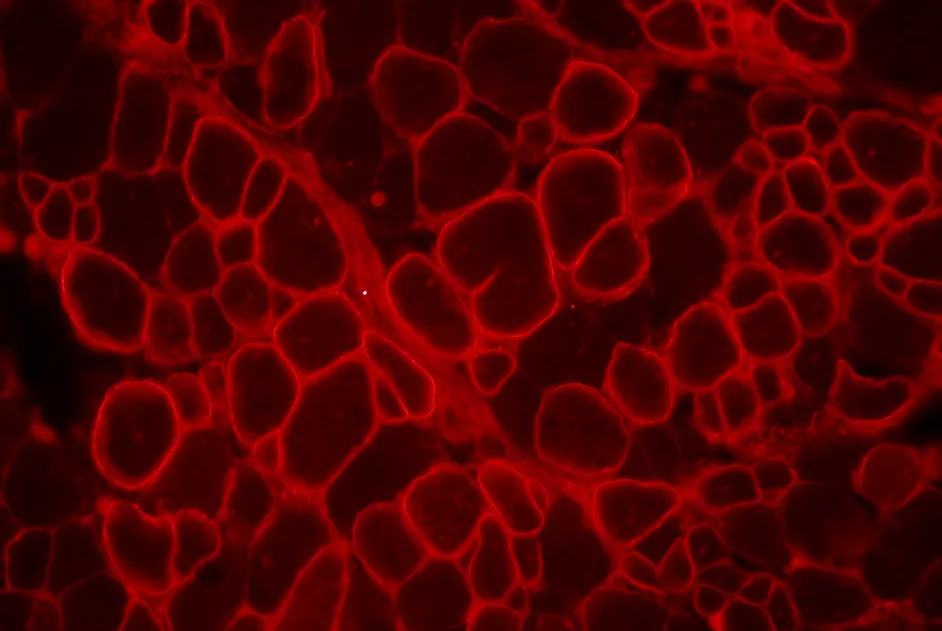

Preuve de concept chez la souris de l’efficacité d’une thérapie inhibant une enzyme de la synthèse du glycogène dans les muscles squelettiques.